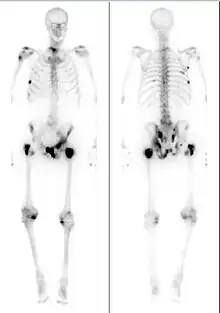

Extent of cancer spread is assessed by MRI or PSMA scan – a positron emission tomography (PET) imaging technique where a radioactive label that binds the prostate protein prostate-specific membrane antigen is used to detect metastases distant from the prostate.[24][20] CT scans may also be used, but are less able to detect spread outside the prostate than MRI. Bone scintigraphy is used to test for spread of cancer to bones.[24]

Advanced prostate tumors often metastasize to nearby bones of the pelvis and back; there they can cause fatigue, unexplained weight loss, and back or bone pain that does not improve with rest.[6] Metastases can damage the bones around them, and around a quarter of those with metastatic prostate cancer develop a bone fracture.[7] Growing metastases can also compress the spinal cord causing weakness in the legs and feet, or limb paralysis.[8][9]

Bone metastases – present in around 85% of those with metastatic prostate cancer – are the primary cause of symptoms and death from metastatic prostate cancer.[55][56] Metastases can cause severe pain and bone weakening, with around 25% of those affected developing a bone fracture.[56] Those with constant pain are often prescribed nonsteroidal anti-inflammatory drugs.[57] However, people with bone metastases often experience "breakthrough pain", sudden bursts of severe pain that resolve within around 15 minutes, before pain medications can take effect.[57] Single sites of pain can be treated with external beam radiation therapy to shrink nearby tumors.[58] More dispersed bone pain can be treated with radioactive compounds that disproportionately accumulate in bone, like radium-223 and samarium-153-EDTMP, which help reduce the size of bone tumors. Similarly, the systemic chemotherapeutics used for metastatic prostate cancer can reduce pain as they shrink tumors.[58] Other bone modifying agents like zoledronic acid and denosumab can reduce prostate cancer bone pain, even though they have little effect on tumor size.[58] Metastases compress the spinal cord in up to 12% of those with metastatic prostate cancer causing pain, weakness, numbness, and paralysis.[59][60] Inflammation in the spine can be treated with high-dose steroids, as well as surgery and radiotherapy to shrink spinal tumors and relieve pressure on the spinal cord.[59][60]